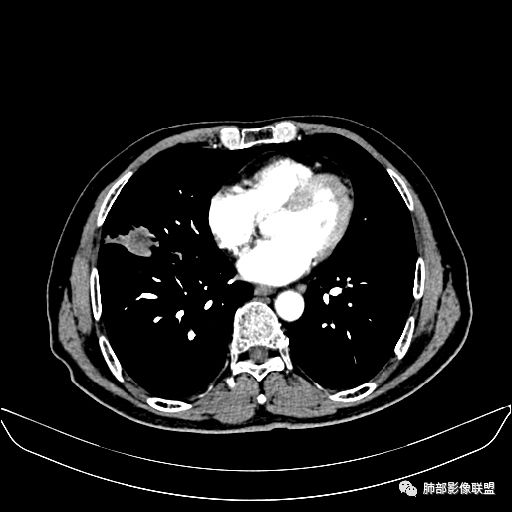

入院CT

老年男性,因“咳嗽咳痰1月余。”入院。病程中咳嗽咳痰,咳黄白痰,间断咯少许鲜红色痰血。PPD阳性。胸CT:右肺中叶外侧段支气管管腔阻塞,大片实性病变,病灶边缘光滑,部分边缘膨隆,可见分叶,肺门及纵隔可见肿大淋巴结,并可见钙化。增强可见病灶明显强化,而且延迟强化明显,病灶内多发低密度区,内见血管影,血管变细、部分血管破坏。考虑恶性病变可能性大,鉴别慢性肉芽肿性病变。

右肺中叶外侧段管腔阻塞、实性病变,病灶边缘光滑,可见分叶,肺门及纵隔可见肿大淋巴结,并可见钙化。增强可见病灶内多发低密度区。

老年男性,咳嗽、咳痰1月余,间断血痰。PPD阳性。

胸CT:跨叶大肿块,主体在中叶,右中叶外侧段支气管阻塞,病灶部分边缘膨隆,可见分叶,部分边缘平直,肺门及纵隔可见肿大淋巴结。增强病灶不均匀强化,延迟强化明显,病灶内多发低密度区,内见血管飘浮,部分血管变细、模糊。考虑:恶性病变可能性大,大细胞?淋巴瘤?鉴别慢性肉芽肿性病变。